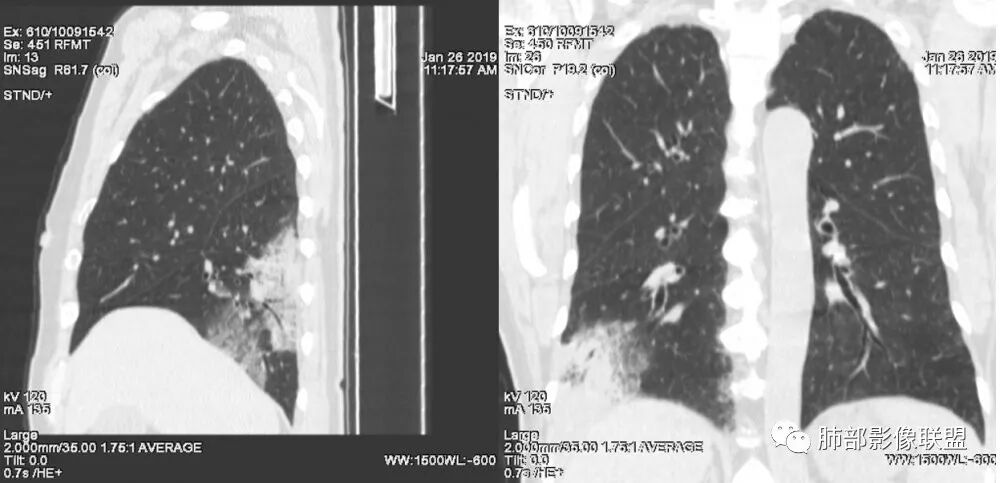

患者中年女性,咳嗽咳痰就诊。胸部CT:右肺下叶后基底段片状实变影,由胸膜向内发展呈扇形,病灶里有小叶内间质增厚、蜂窝状影,周围边界清楚GGO,内可见扩张支气管,淋巴结无明显肿大。综合符合粘液腺癌。

老年女性;右下肺混合实变影,呈楔形改变,边缘清晰,支气管进入且扩张,蜂窝状改变,考虑粘膜相关淋巴瘤,鉴别粘液腺癌,肺栓塞。

老年女性,咳嗽、咳痰。右肺下叶沿胸膜下大片状高密度影,外周磨玻璃影,边界较清,小空泡,蜂窝征及支气管充气征,叶间裂串珠征,考虑:肺炎型肺癌,鉴别:肺克,链球菌,NTM等感染。

老年女性,右肺下叶大片实变,小叶间隔及小叶内间隔增厚,边界较清,其内支气管似乎可见稍扭曲,分支减少。考虑1.肺炎型肺癌2.结合临床除外类脂性肺炎。

右肺下叶胸膜下大片状MGGO,其内结构紊乱,可见空泡征,病灶内近端支气管扩张,远端闭塞,形态不规则,边界部分清楚,部分似清非清,考虑粘液腺癌,鉴别淋巴瘤

1.本例病灶较大片混杂密度影,胸膜下分布为主(未沿着支气管分布),该分布特点可见于大叶性肺炎、干酪性肺炎、淋巴瘤及粘液腺癌等。可惜未提供增强扫描图像。

2.病灶示中央实变区,周围GGO,可见明显小叶间隔增厚,GGO边界清楚,应当考虑到恶性病变的可能性。肺炎因炎性水肿及渗出,影像上边界常模糊不清,注意早期粘液腺癌可出现似清非清的边界。粘液腺癌因粘液成份较多,密度一般偏低,纵隔窗病灶常会消隐或范围会明显缩小,这不同于炎性实变。

3.病灶内支气管走形略显僵直,侧支少(粘液阻塞),也符合肺腺癌的枯树枝征。而大叶性肺炎的支气管是管壁光整、通畅、自然,结核的支气管常常壁增厚,甚至狭窄后扩张;

4.患者临床症状不重,临床炎性指标不高,结合肺内影像,应警惕肺炎型肺癌。